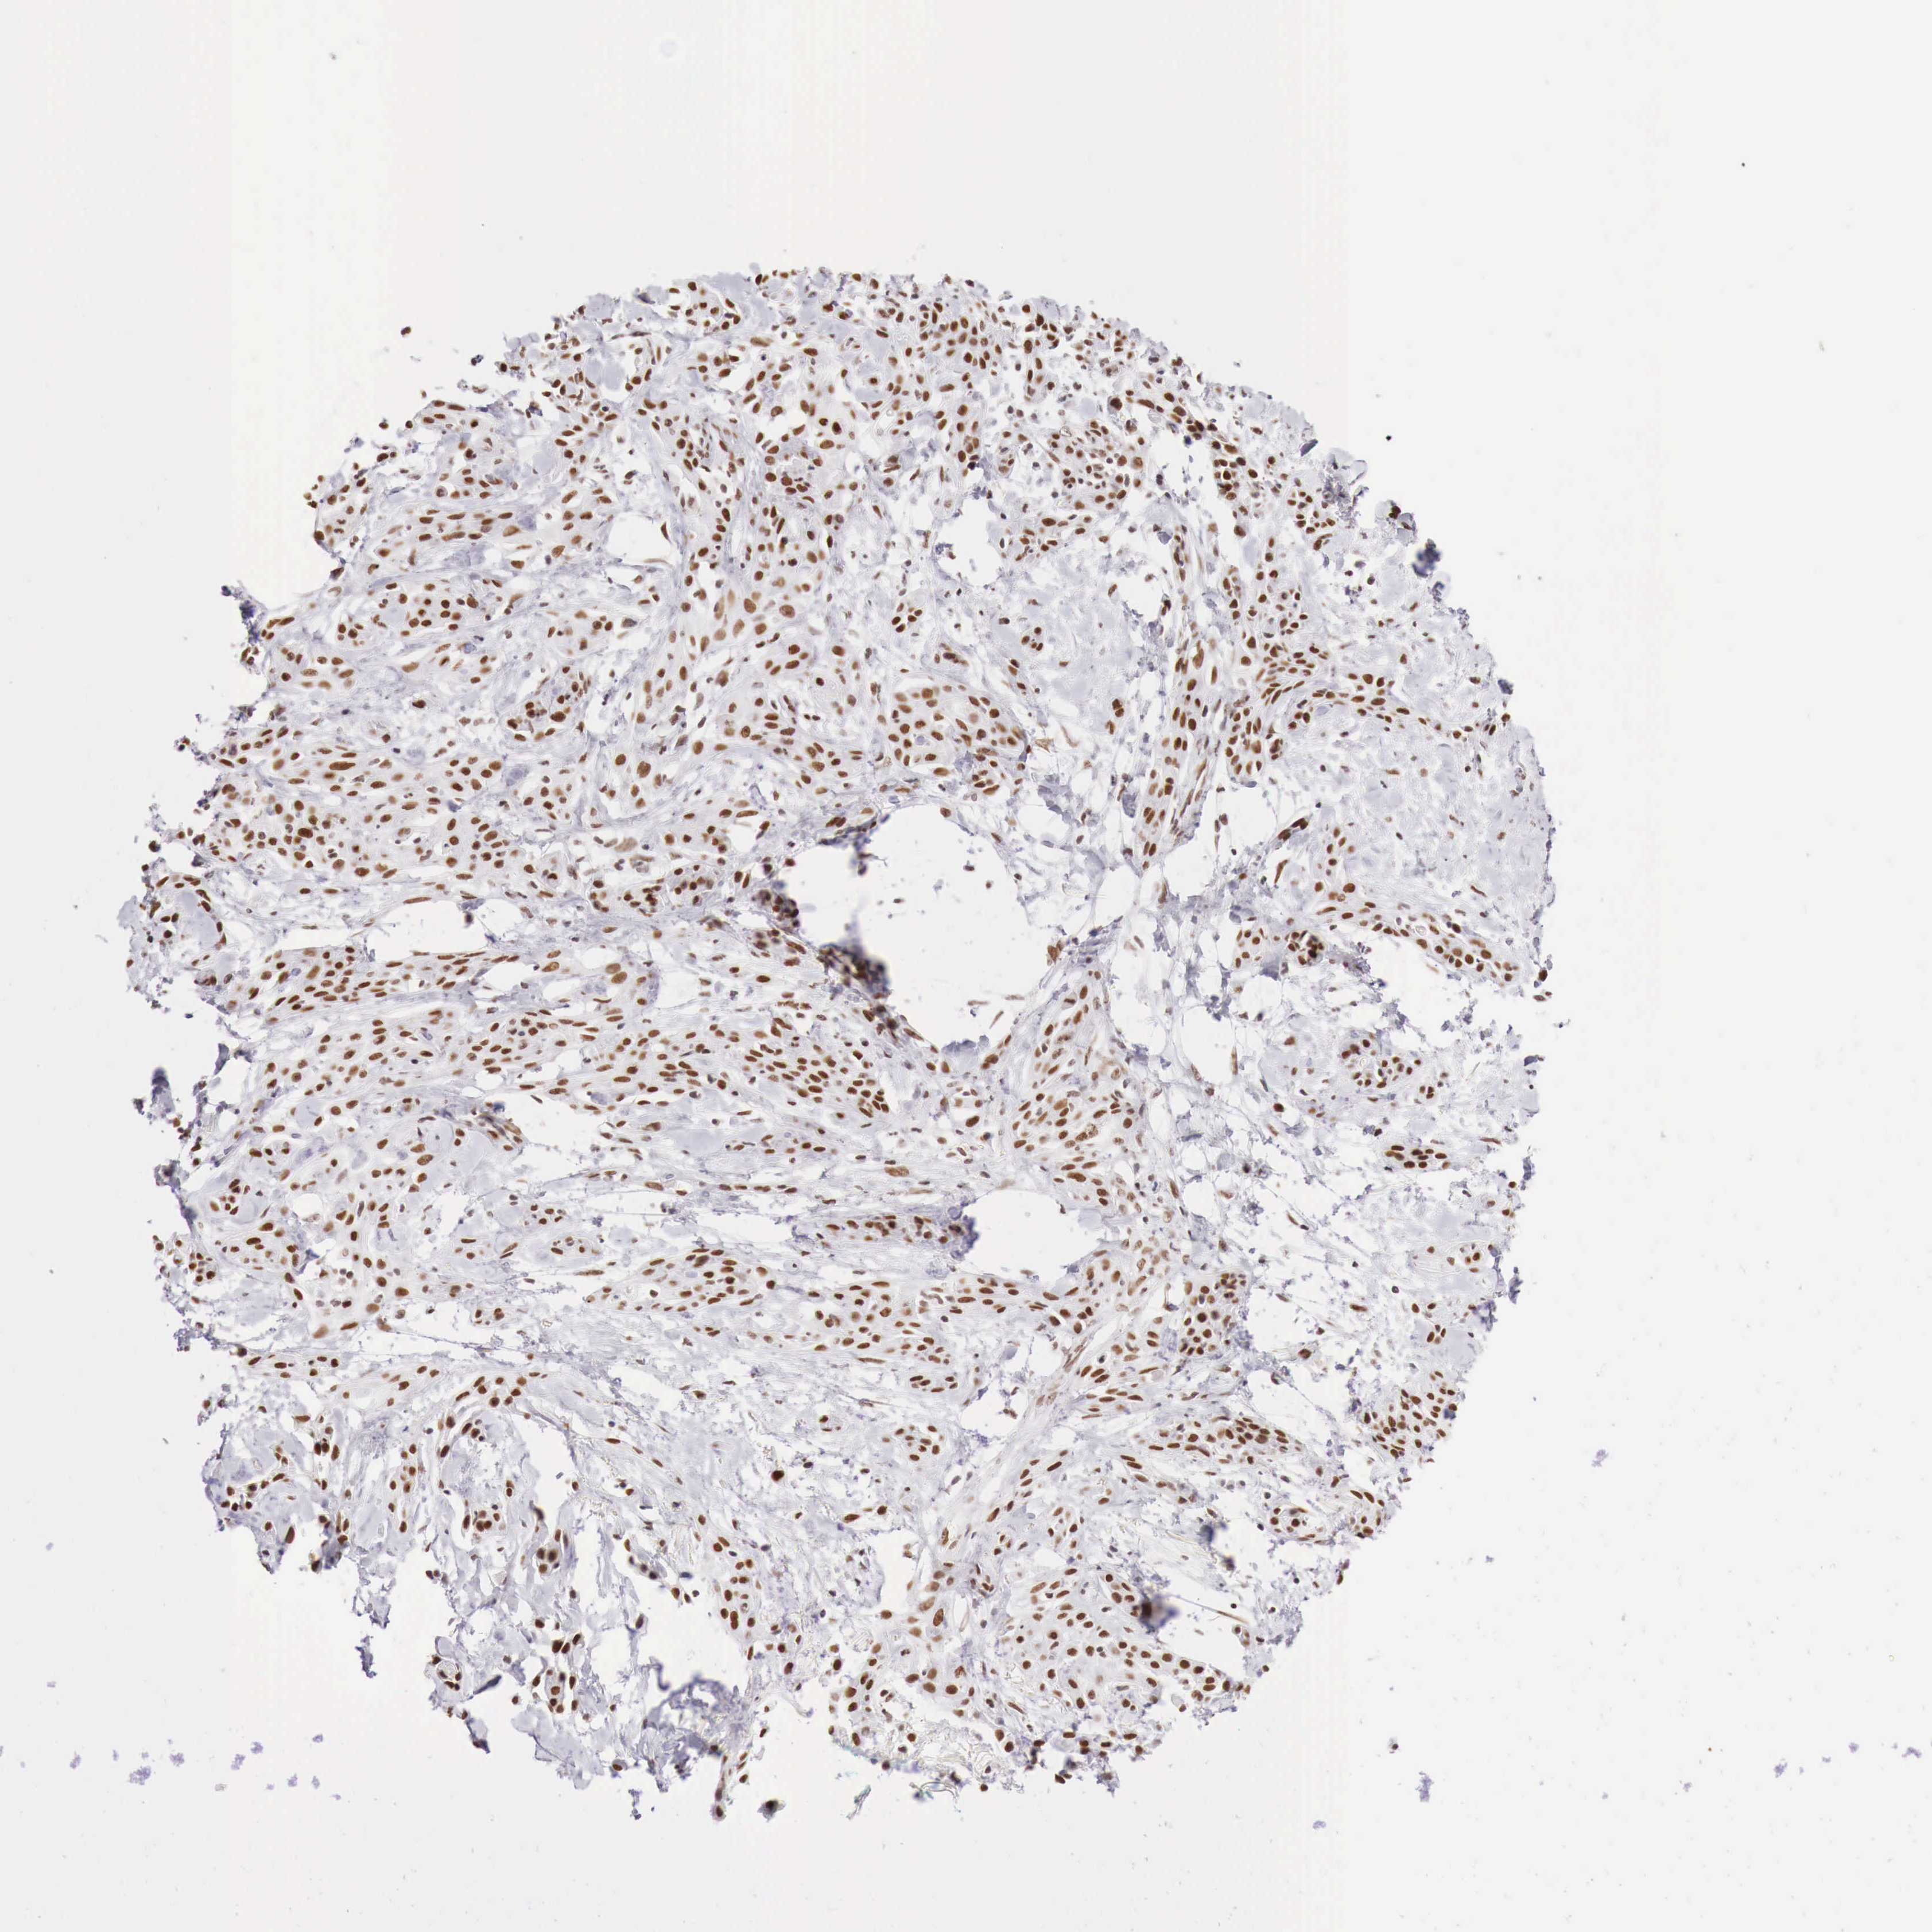

SKIN CANCER - Protein expressioni

A mouse-over function shows sample information and annotation data. Click on an image to view it in a full screen mode. Samples can be filtered based on level of antibody staining by selecting one or several of the following categories: high, medium, low and not detected. The assay and annotation is described here.

Antibody staining in the annotated cell types in the current human tissue is reported as not detected, low, medium, or high, based on conventional immunohistochemistry profiling in selected tissues. This score is based on the combination of the staining intensity and fraction of stained cells.

Each image is clickable and will lead to virtual microscopy that enables deeper exploration of all samples and also displays staining intensity scores, fraction scores and subcellular localization as well as patient and tissue information for each sample.

Antibody HPA000538

Staining

Medium

Intensity

Moderate

Quantity

75%-25%

Location

Nuclear

Basal cell carcinoma